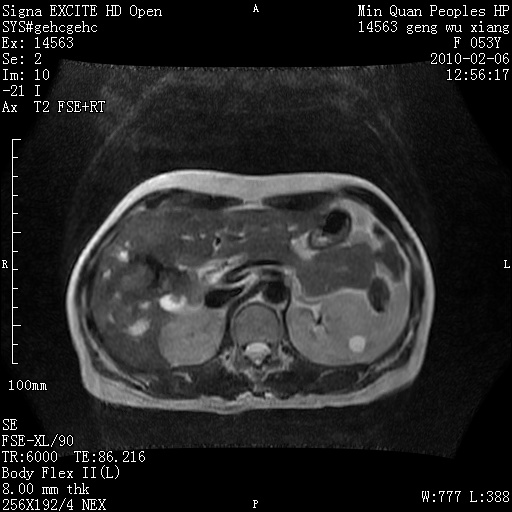

标题: MRI2762:胆道梗阻原因?

f,53y,全身黄染多日。

高位胆道梗阻 胆管癌可能性大

支持 高位胆道梗阻 胆管癌可能性大。